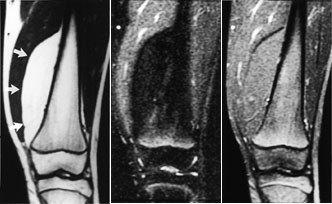

Ved osteogent sarkom og Ewings sarkom kan MR med snittplan i knokkelens lengdeakse nøyaktig fastslå øvre og nedre grense for tumorutbredelse i beinmargen (fig 5), påvise metastaser innenfor samme margrom og innvekst i ledd. Dette er forhold som har stor betydning for omfanget av kirurgiske inngrep. Som regel har tumor på diagnosetidspunktet brutt gjennom knokkelen og gitt opphav til en ekstraossøs komponent. Med snittplan perpendikulært på knokkelen kan MR vise om tumor affiserer kar og nerver, og hvilke muskler den ligger an mot eller infiltrerer. MR kan styre biopsitakingen til de områder av tumor hvor det er størst sannsynlighet for å finne representativt vev.

Konvensjonelle røntgenbilder er første trinn i utredningen av mistenkte bløtvevssvulster (12). De viser underliggende skjelettdeformitet, beinaffeksjon og bløtvevsforkalkninger. Forkalkninger kan ikke påvises med MR. MR er allikevel den beste metoden, fordi den i tillegg til å vise de anatomiske forhold også fremstiller væske, nekrose, blødning, fett og annet bløtvev (fig 6 – 8). Basert på vekstmønster og signalforhold kan vevsspesifikk diagnose stilles i 20 – 40 % av tilfellene. Det er oftest ikke mulig å angi om en bløtvevstumor er benign eller malign. Nekrose er den enkeltfaktor som sterkest peker i retning av malignitet. Andre faresignaler er stor tumor, uskarp avgrensning med omgivende ødem, heterogent signal og beinaffeksjon. Men høymaligne bløtvevssvulster kan være velavgrenset med en pseudokapsel.